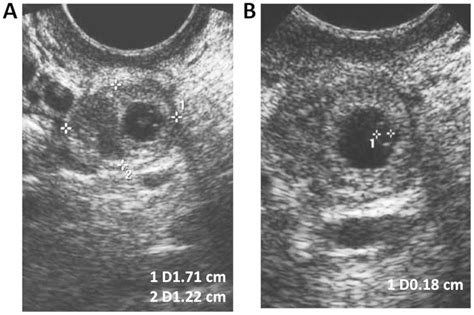

• The ectopic mass is typically measured to be smaller than 3.5 to 4 centimeters.

If you have had an ectopic pregnancy, your risk of a future ectopic pregnancy may be slightly higher. Therefore, once you conceive again, it is important to notify your obstetrician early so that they can perform an early ultrasound to confirm that the pregnancy is intrauterine and developing normally.